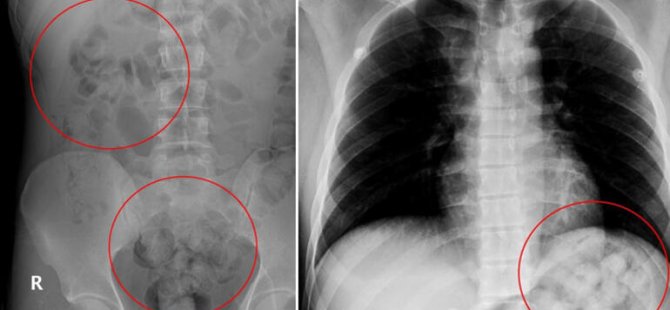

Ankara’da yabancı uyruklu Zadeh Ahmed Narziveh, şehirlerarası otobüs terminali AŞTİ’de fenalaştı. Hastaneye kaldırılan Narziveh’in çekilen röntgeninde midesinde uyuşturucu kapsülleri görüldü. Ameliyata alınan Narziveh’in midesinde 2’si patlamış, 72 kapsül halinde 890 gram uyuşturucu madde metamfetamin çıkarıldı.